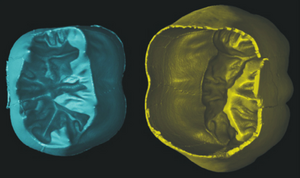

Publication: Sci Rep. 2015 Dec 14;5:18156. PMID: 26657471 | PDF Authors: Hagen CK, Maghsoudlou P, Totonelli G, Diemoz PC, Endrizzi M, Rigon L3, Menk RH, Arfelli F, Dreossi D, Brun E, Coan P, Bravin A, De Coppi P, Olivo A. Institution: University College London, Department of Medical Physics and Biomedical Engineering, London, UK. Background/Purpose: Acellular scaffolds obtained via decellularization are a key instrument in regenerative medicine both per se and to drive the development of future-generation synthetic scaffolds that could become available off-the-shelf. In this framework, imaging is key to the understanding of the scaffolds' internal structure as well as their interaction with cells and other organs, including ideally post-implantation. Scaffolds of a wide range of intricate organs (esophagus, lung, liver and small intestine) were imaged with x-ray phase contrast computed tomography (PC-CT). Image quality was sufficiently high to visualize scaffold microarchitecture and to detect major anatomical features, such as the esophageal mucosal-submucosal separation, pulmonary alveoli and intestinal villi. These results are a long-sought step for the field of regenerative medicine; until now, histology and scanning electron microscopy have been the gold standard to study the scaffold structure. However, they are both destructive: hence, they are not suitable for imaging scaffolds prior to transplantation, and have no prospect for post-transplantation use. PC-CT, on the other hand, is non-destructive, 3D and fully quantitative. Importantly, not only do we demonstrate achievement of high image quality at two different synchrotron facilities, but also with commercial x-ray equipment, which makes the method available to any research laboratory. Funding:

Images acquired with synchrotron-based PC-CT showing a rat small intestine that was decellularized via DET: (a) transverse cross section, (b) three-dimensional view. All scale bars represent 500 μm. Images were processed using the ESRF in-house software PyHST, and analyzed and displayed with ImageJ31 and 3D Slicer. |